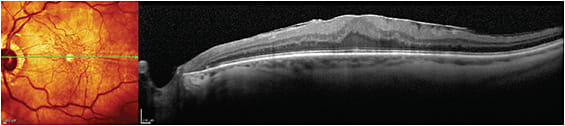

Left eye with severe vitreomacular traction syndrome.

IMAGE COURTESY STEVEN G. SAFRAN, MD

Right eye with lamellar macular hole.